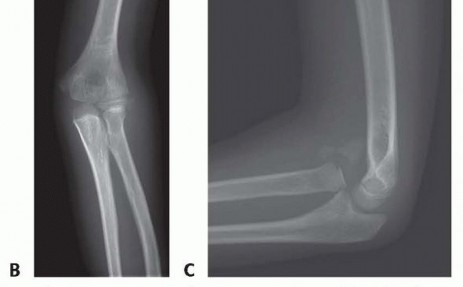

FIG 1 • Chronic Monteggia lesion in a 7-year-old girl with a 5-week history of elbow pain and loss of motion following trauma. A. Initial lateral forearm radiograph demonstrates an abnormal ulnar bow line, or deviation of the ulna from its normally straight dorsal border, and is suggestive of plastic deformation. Anterior dislocation of the radial head is also noted. These findings were not detected in the emergency department where dedicated elbow films were not obtained, and the child was diagnosed with an elbow sprain. B. AP elbow radiograph 5 weeks after injury demonstrates a normal radiocapitellar line with a poorly characterized calcification overlying the lateral aspect of the capitellum. On the AP view, the radiocapitellar line is often normal in acute or chronic Bado type I Monteggia lesions. C. Lateral elbow radiograph 5 weeks after injury demonstrates disruption of the radiocapitellar line and anterior translation of the radial head. There is calcification of the displaced annular ligament and anterior elbow capsule, which can be mistaken for heterotopic ossification.